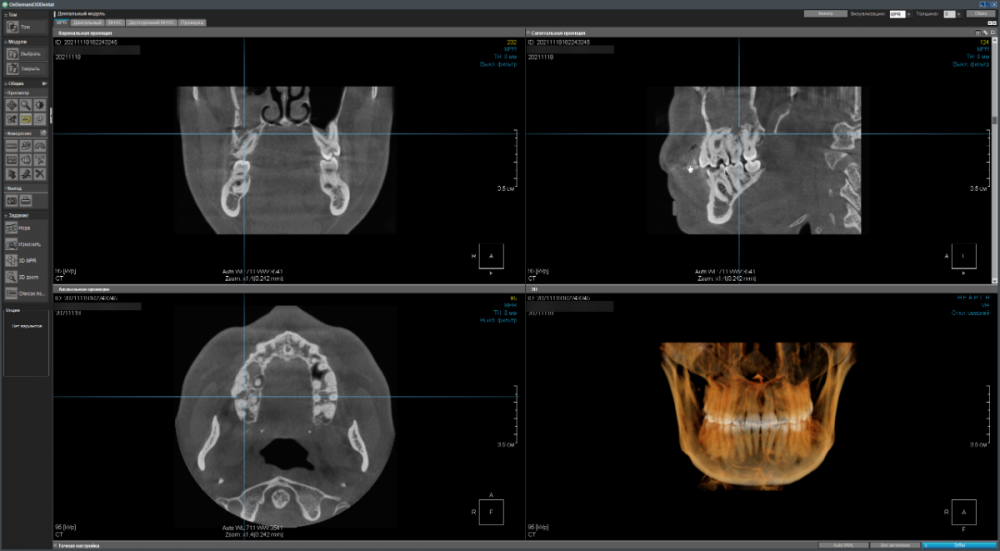

Имеется два сильно запущенных зуба на верхней челюсти справа - хотелось бы понять имеет ли смысл пытаться вылечить их терапевтически (чтобы потом поставить коронки) или уже поздно и надо/лучше удалить (и установить импланты)?

CDViewer_yU53R3mCpM.png